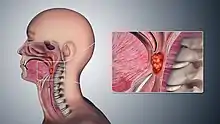

| 3D medical illustration showing the cancer formation in the tissues of the oropharynx | |

Oropharyngeal cancer,[1][2][3] also known as oropharyngeal squamous cell carcinoma and tonsil cancer,[1] is a disease in which abnormal cells with the potential to both grow locally and spread to other parts of the body are found in the oral cavity, in the tissue of the part of the throat (oropharynx) that includes the base of the tongue, the tonsils, the soft palate, and the walls of the pharynx.[1][2][3][5]